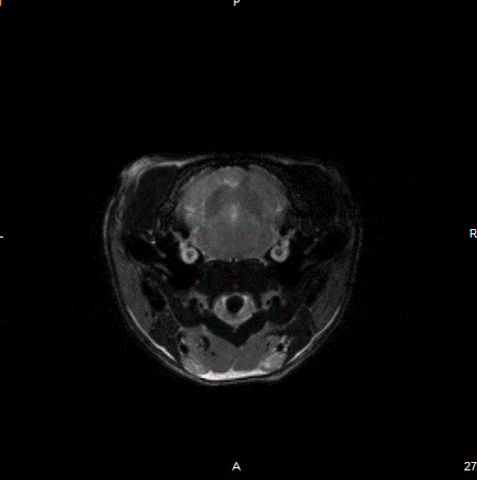

Cardiac Cine loop images: Long axis view of a single slice of the heart was acquired with Cine loop images. Long axis images can be used for strain analysis in third party softwares.

Cardiac Cine loop images: Long axis view of a single slice of the heart was acquired with Cine loop images. Long-axis images can be used for strain analysis in third-party software. Image Credit: Scintica Instrumentation Inc

Short axis view of a single slice of the heart was acquired with Cine loop images. Short axis images can be used for analysis of functional measurements in third party softwares

Short axis view of a single slice of the heart was acquired with Cine loop images. Short axis images can be used to analyze functional measurements in third-party software. Image Credit: Scintica Instrumentation Inc